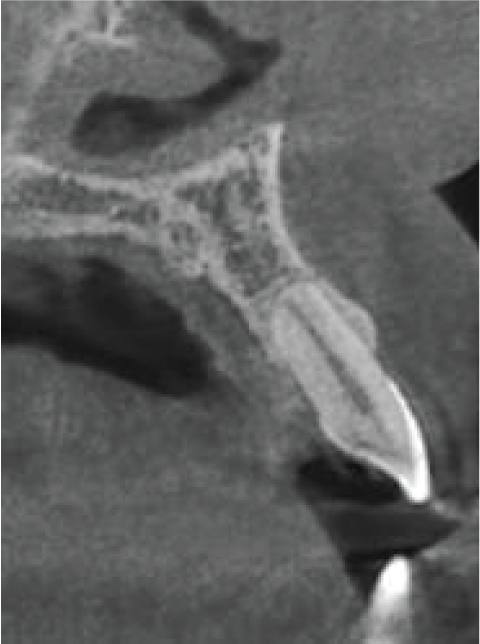

The UL2 has a flat root end, consistent with apical resorption. There is no associated bony pathosis, so this is probably old and non-progressive resorption (image 5).

Image 5. Bucco-palatal cross section of UL2